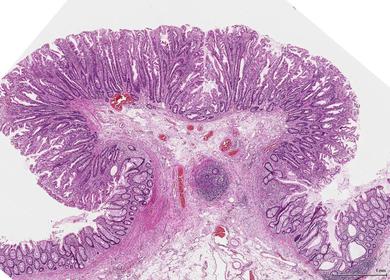

TISSUE TYPE: villi of intestine PATHOLOGY: protrusion of mucosa and submucosa upwards.. bilharizial ova in sub. DIAGNOSIS : bilharizial intestinal polyp KEY: TREE LIKE PROTRUSION..